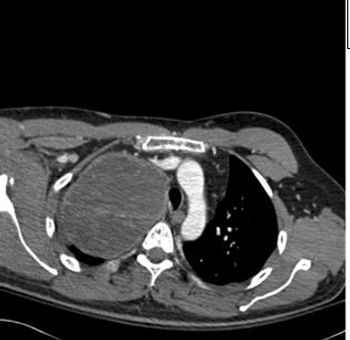

Two weeks after injury to the right chest wall and shoulder, the patient continues to have pain. He also reports numbness and tingling in his hands bilaterally. What do the ED images reveal?

Results of a physical examination and CT scan of the chest offer clues to this patient's diagnosis.